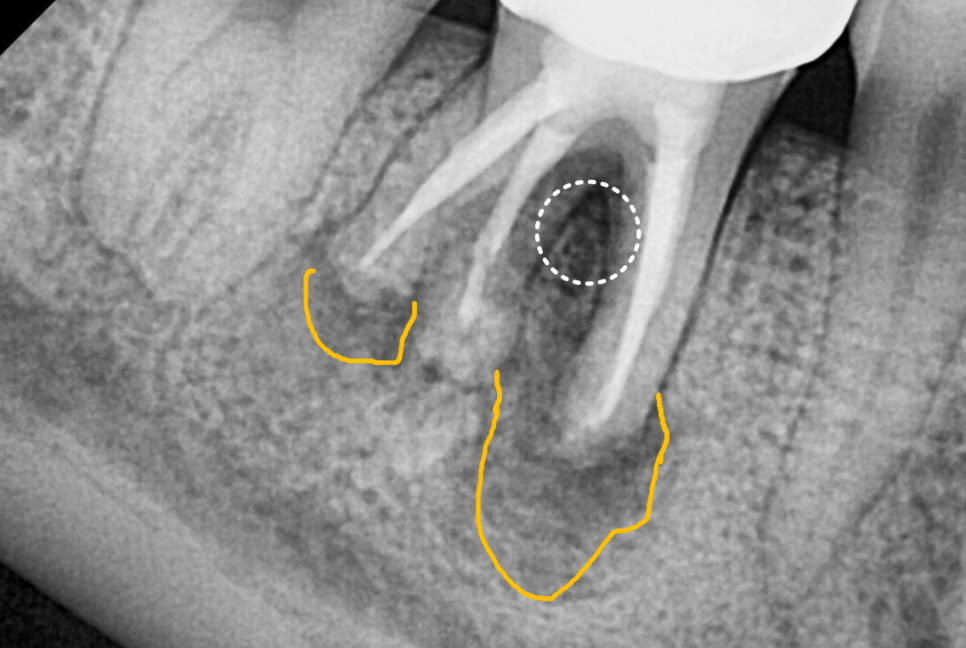

이미 신경치료는 다 되어 있고

사진상에도 치아 뿌리에

염증이 심하게 생긴 상태였어요.

250602 뿌리 끝 염증으로 뼈가 녹은 상태

CT를 찍어보니 뼈 소실이 생각보다 많이 진행되어 있었습니다.